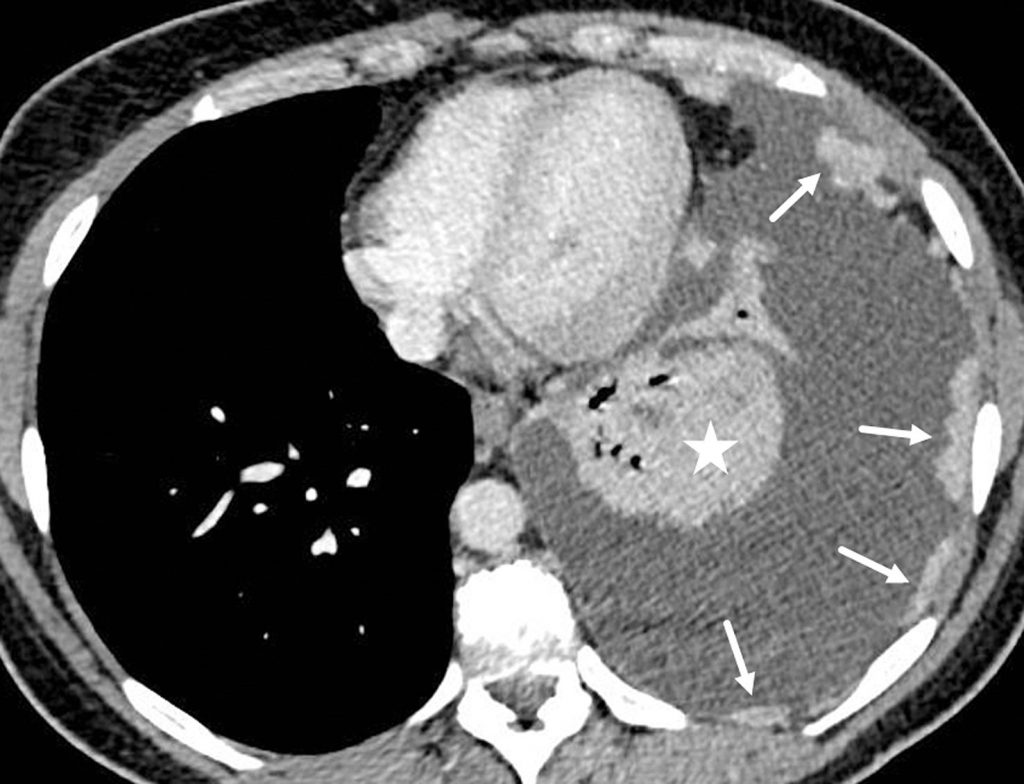

Fig. 91.10. Scanner d’une pleurésie carcinomateuse.

Volumineux épanchement pleural gauche associé à des épaississements pleuraux nodulaires rehaussés par le produit de contraste (flèches). Le parenchyme pulmonaire gauche est totalement collabé (étoile).

Source : CERF, CNEBMN, 2022.